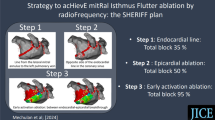

For LSPV, freezing characteristics are shown in Table 3 and Fig. 1.

Time–temperature graph for cryoablation in the left superior pulmonary vein (LSPV) using AFA-Pro (n = 65 patients) and POLARx (n = 92 patients). Only patients with an ablation cycle duration of 240 s were included. The solid line corresponds to the mean, and the dashed line to the standard deviation

For LIPV, RSPV, and RIPV, see Supplementary Table S4 and Supplementary Fig. S1.

With an average duration of 244.1 ± 54.7 s for AFA-Pro, the first ablation cycle of the LSPV was significantly longer compared to the POLARx CB with a duration of 227.9 ± 29.1 s (p = 0.006). This effect was also observed for LIPV. However, the total freeze time was comparable between both CBs in all PVs, including the LSPV (AFA-Pro: 271.1 ± 96.5 s vs. POLARx: 277.1 ± 150.1 s, p = 0.719). Additionally, there was no significant difference in the number of total freezes for all PVs.

The cooling profile analysis revealed distinct differences between the two CBs in terms of temperature characteristics and their ability to achieve and sustain low temperatures. POLARx achieved lower minimal temperatures in all PVs compared to AFA-Pro (e.g., LSPV: − 59.5 °C (− 62, − 55) vs. − 49 °C (− 53, − 46), p < 0.001) and lower temperatures at TTI (e.g., LSPV: − 48 °C (− 50, − 44) vs. − 39 °C (− 42.5, − 35), p < 0.001). Furthermore, the POLARx CB exhibited significantly lower temperatures after 40 and 60 s, as well as a larger mean temperature change between 20 and 40 s (e.g., LSPV: AFA-Pro − 1.2 ± 0.2 °C/s vs. POLARx − 1.8 ± 0.3 °C/s, p < 0.001). Consistent with these findings, POLARx reached low temperatures, such as − 40 °C, faster than AFA-Pro. The cooling performance of POLARx was further underscored by a significantly greater area under the curve (AUC) below 0 °C. Correspondingly, the thawing phase to reach 0 °C was significantly longer with POLARx compared to AFA-Pro (LSPV: AFA-Pro: 11.0 (8.0, 14.0) s vs. POLARx: 21.0 (17.0, 24.0) s, p < 0.001). With regards to safety, the minimal esophagus temperature in all PVs did not differ significantly between the two systems (e.g., LSPV: AFA-Pro: 34.25 °C (30.15, 35.40) vs. POLARx: 33.40 °C (29.80, 35.30), p = 0.666).